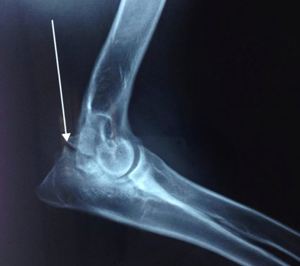

骨軟骨病是一種關(guān)節(jié)軟骨和骺軟骨軟骨內(nèi)骨化障礙的非炎性疾病。臨床上常見的骨軟骨病有如下幾種:①分離性骨軟骨??;②肘突不閉合;③尺骨冠狀突分裂;④骺生長板骨化遲滯。